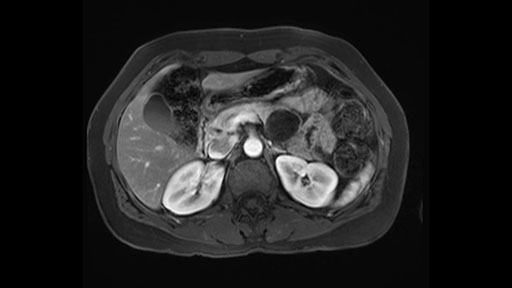

In reviewing this patient’s CT scan, first of all, the lesion is again cystic with a very thin wall. I anticipate that it will be delicate and potentially friable. And therefore the risk of rupture exists and we need to be very careful in how we handle the pancreas and the tumor throughout the procedure.

The lesion itself is quite adjacent to and abuts the splenic vein and therefore we need to anticipate that these two structures will be intimately related and possibly impossible to separate between the two.

The lesion also is quite posterior. While the plane between the cyst and the left adrenal gland is often preserved, we do have to pay attention here so that we remain in the right plane and maintain our margin here. Occasionally in these cases, en bloc adrenalectomy needs to be performed.

In terms of maintenance of the regular planes, other factors that we need to consider is whether you need to enter in posteriorly to Gerota’s fascia to obtain an adequate margin and anteriorly to ensure the tumor can be mobilized safely off of the posterior wall of the stomach.

In light of these findings, on the cross sectional imaging which include MRI, our plan would be to perform a laparoscopic distal pancreatectomy. I think based on oncologic grounds, a spleen preserving procedure is probably reasonable. From looking at the scan, its likely technically possible although a vessel preserving procedure is likely not appropriate for this patient. Technical intraoperative factors will certainly influence that decision.